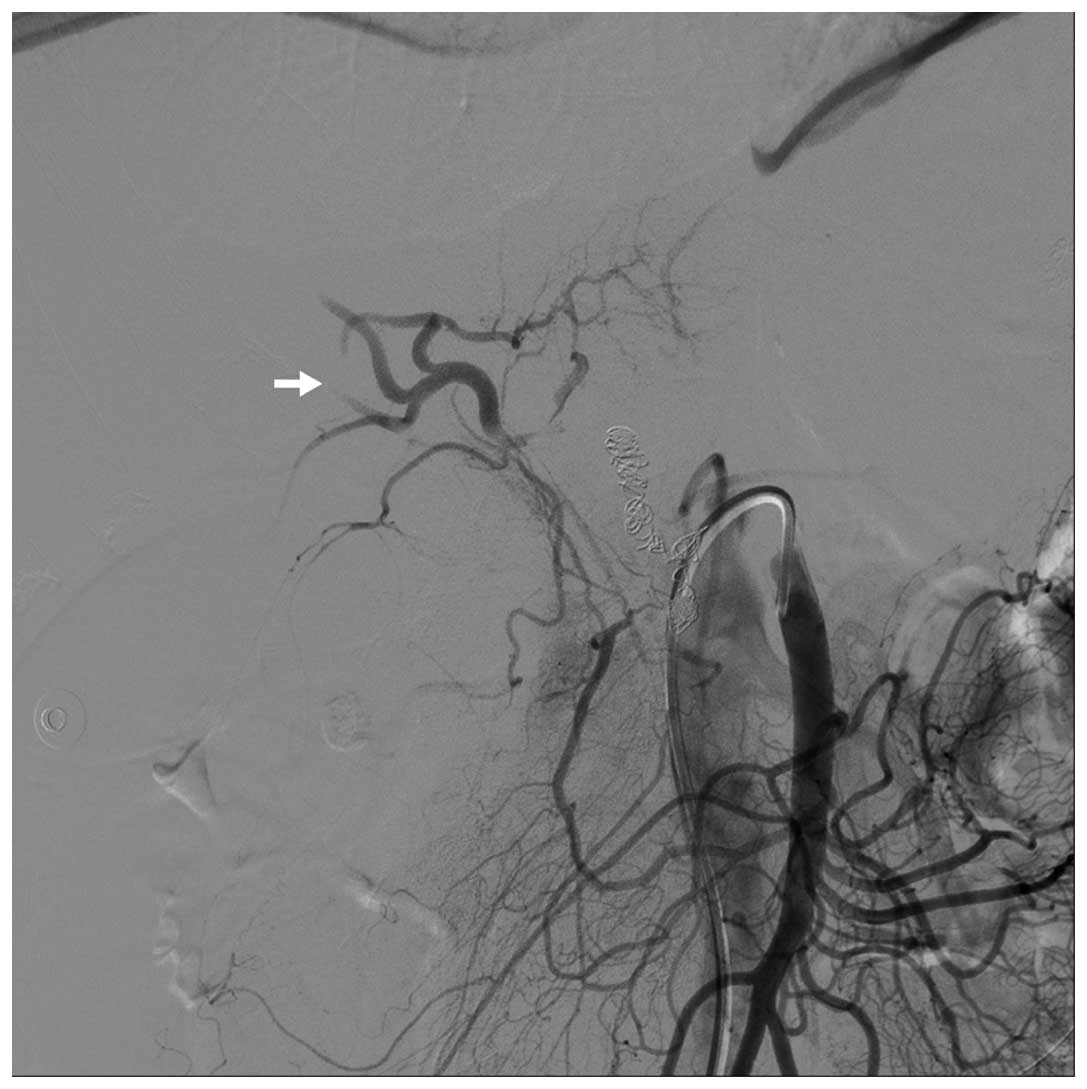

Что такое эмболизация сосудов при аденоме простаты - фото презентация